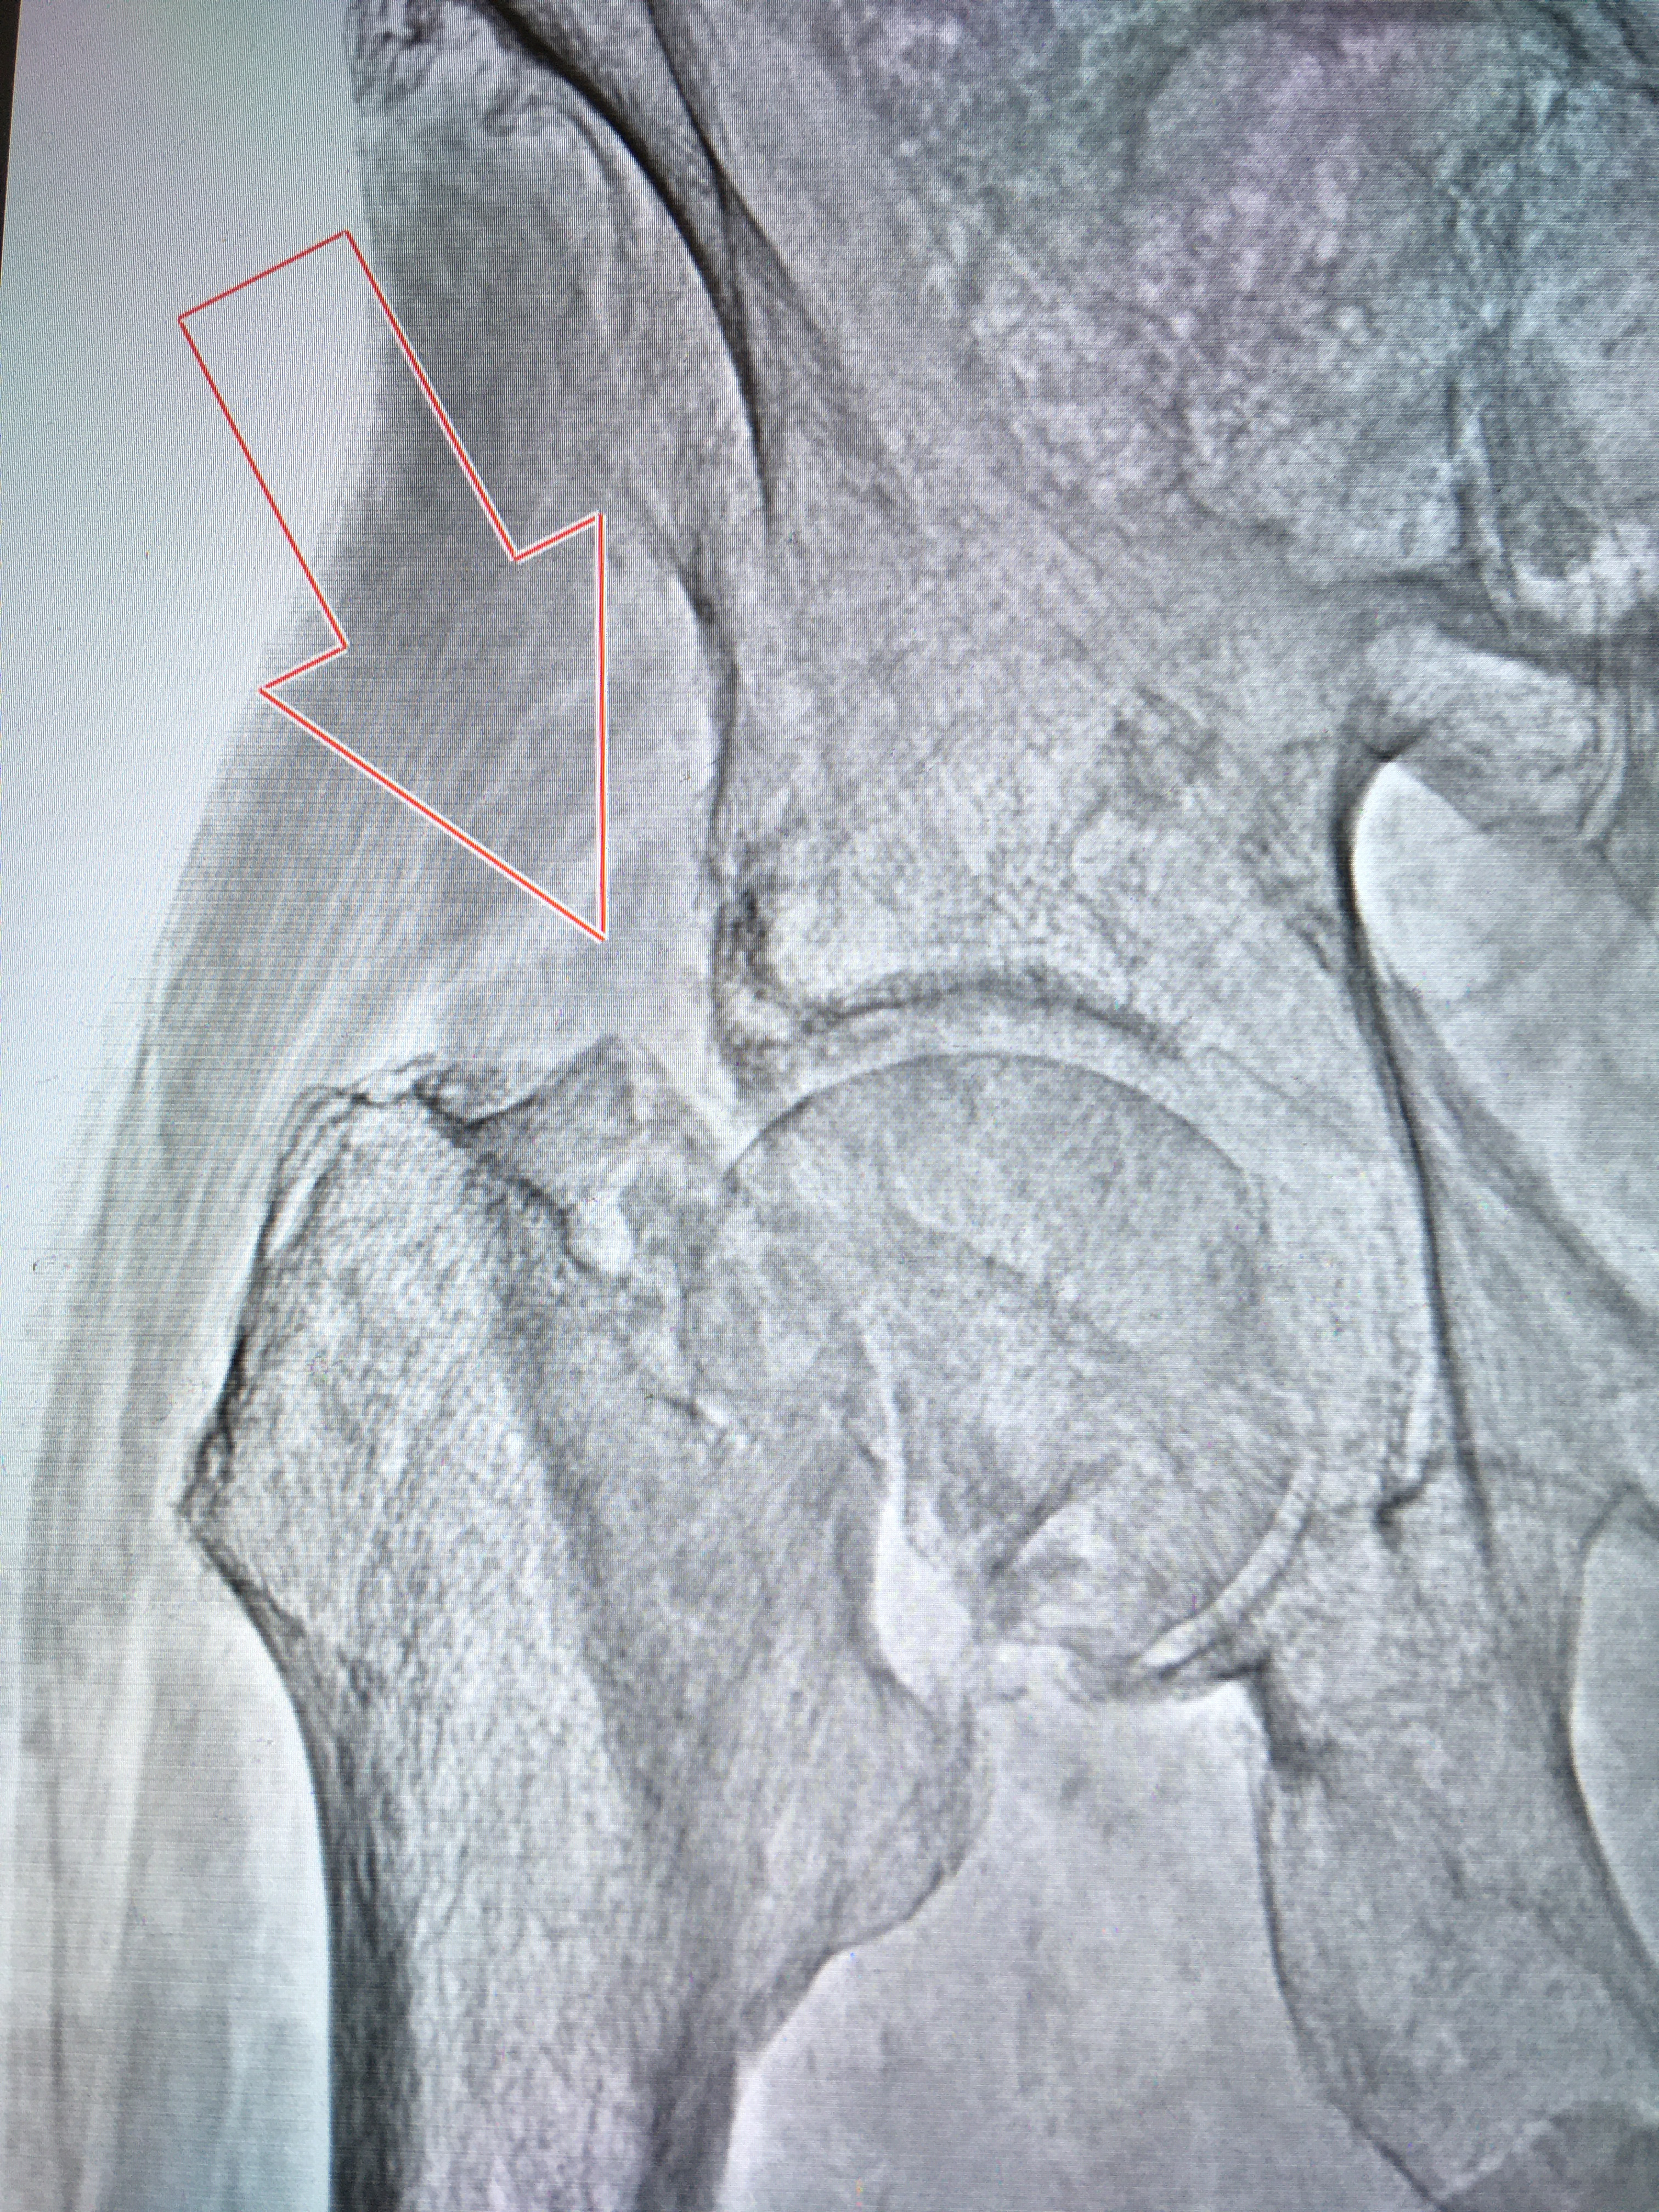

Перелом шейки бедра от 27042021

Рентген на дому: по вашему адресу приезжает врач-рентгенолог, травматолог-ортопед с мобильным рентгеновским аппаратом, проводит диагностику травмы или заболевания, делает необходимые рентгенограммы, дает рекомендации по дальнейшему лечению. Получить качественные снимки в домашних условиях возможно благодаря уникальной методике, разработанной МосРентген Центром для института  Склифосовского